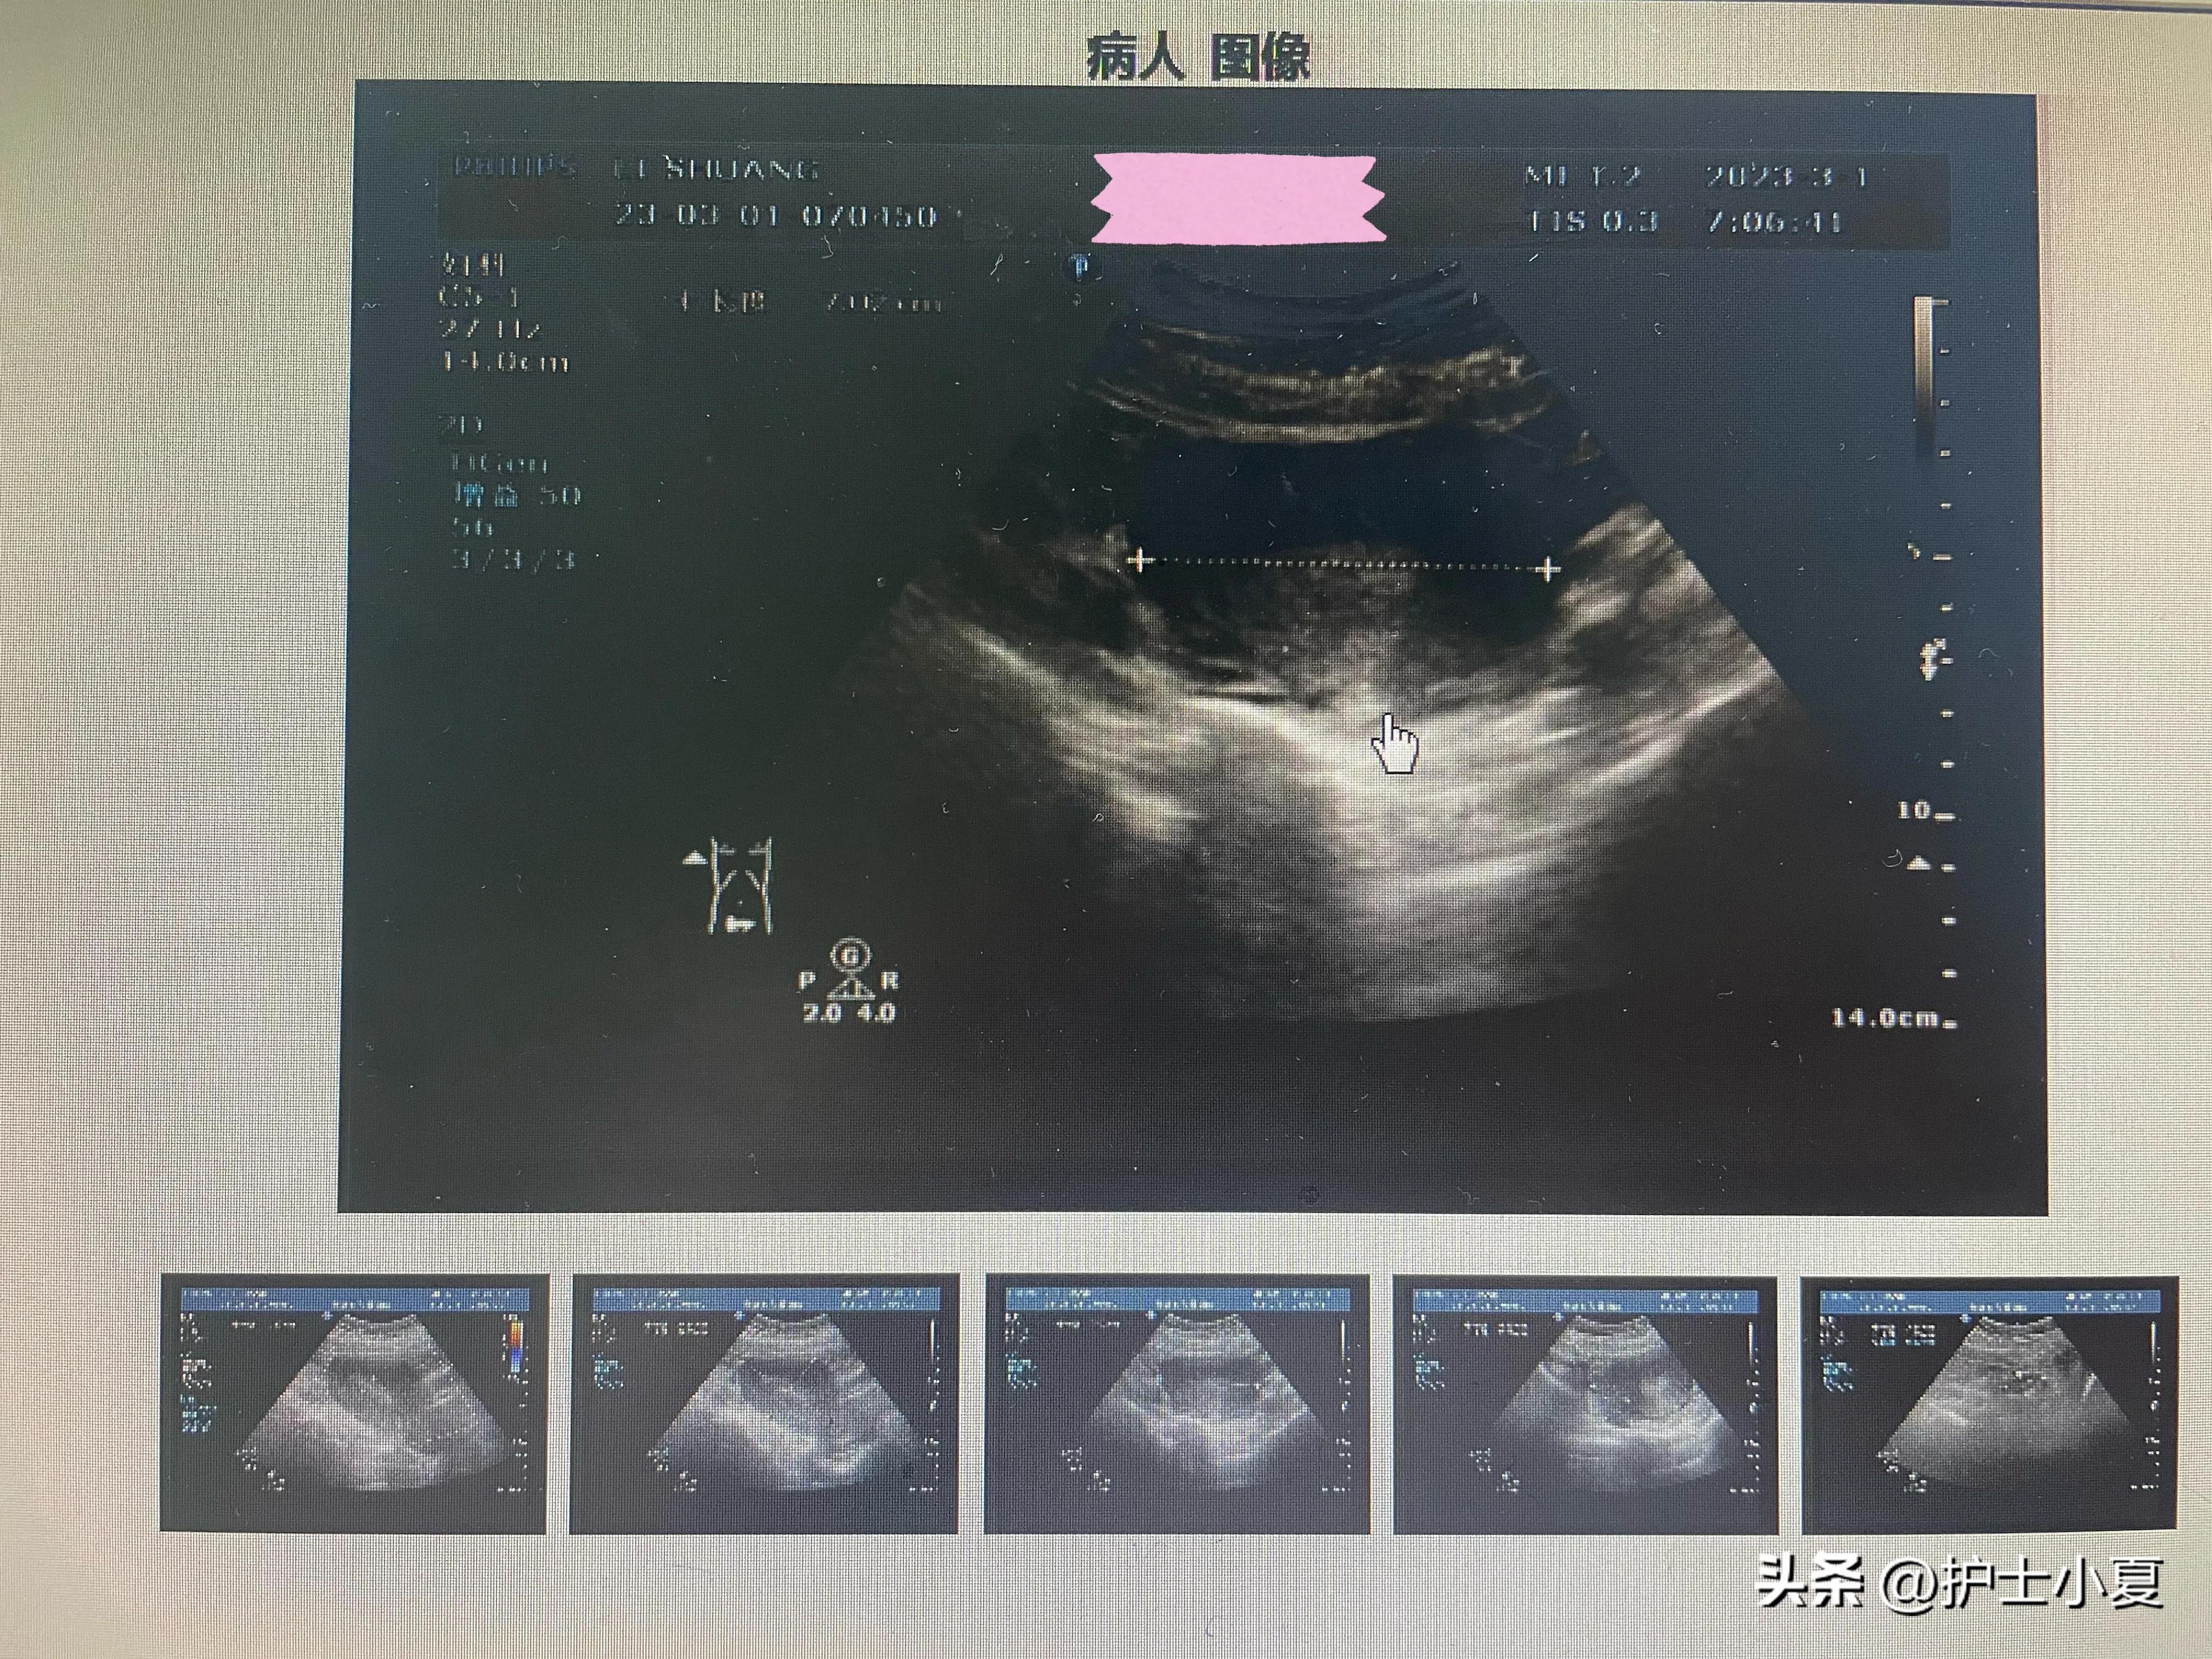

引产产后第二天 ,无发热、腹痛等不适,饮食睡眠好,二便正常。查体:平温脉,SPO:99%,双乳软,无压痛,未泌乳,心肺听诊未闻及异常,腹软、无压痛、宫底位于耻骨联合上一横指,会阴体无水肿,阴道血性恶露少许、无异味,四肢活动自如。复查超声提示:子宫体大小约83*70*58mm,轮廓整,宫体回声均匀,内膜厚约13mm。左卵巢大小约32*18mm:右卵巢大小约42*22mm。